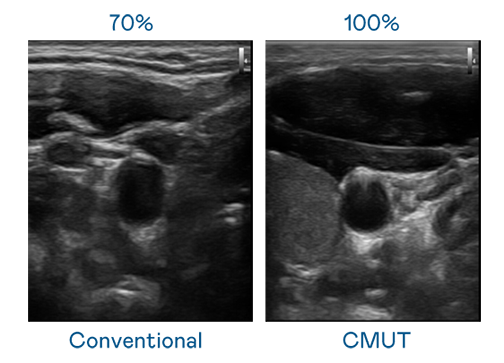

CMUT 技术是一种用电容式微机电元件来产生超音波讯号的技术。与传统 PZT 压电式技术相比,CMUT 频宽增加 30%,更宽频的超音波讯号让影像解析度大幅提升,是实现高影像品质医疗超音波扫描、促进精准医疗发展的关键技术。

大频宽带来超清晰影像

超音波影像的解析度高低,首先取决于探头能发出的讯号频宽。众腾娱乐 CMUT 可提供高清晰的超音波讯号,提供高频宽、高灵敏度、影像纹理细节更高的超音波影像,协助医护人员缩短影像判读时间及利用精准的医疗影像进行诊断。